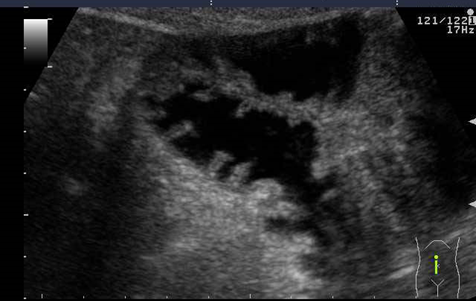

Diaqnostika. Anamnestik məlumatlar (düz bağırsaqdan periodik qanaxmalar, residiv qarın ağrıları, nəcis ifrazının qəbizliyə meylliliyi), palpator kütlə əllənməsi, kontrastlı RH-ji və KT müayinələri (genişlənmiş proksimal (gətirici) bağırsaq ilgəyi, kontrastın haçalanması, kəskin hallarda üfuqi maye-qaz səviyyələri), laparoskopiya diaqnozun qoyulmasında çox mühümdür.

Differensial diaqnostika. Qarın boşluğunun istənilən həcmli törəməsi, xüsusilə limfangiom, mezenterial sist(om); azan, hərəkətli böyrək. Mezenterial sist(om) və limfangiomun əzələ toxuması olmur, divaları incədir, çoxhücrəli (kameralı) olurlar, müstəqil damarları hesabına qan təchizi bağırsaqdan ayrı olur.